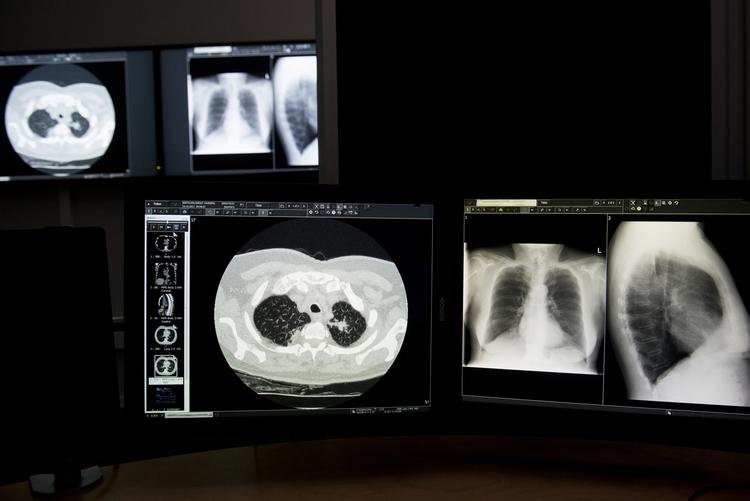

Det nationale selskab for lungekræft (DLCG) anbefaler en fuld CT-scanning af brystkasse og mave ved selv den mindste mistanke om lungekræft.

På trods af denne retningslinje har Diagnostisk Center i Silkeborg under ledelse af den pågældende overlæge tilbudt lavdosis CT-scanninger (LDCT) til udredning af patienter.

Forskning fra andre lande viser, at der er en risiko for falsk positive resultater ved brugen af lavdosis CT-scanninger. Man kan også risikere at overse lungekræft, skriver regionen.

Diagnostisk Center har siden 2015 tilbudt lavdosis CT-scanning til udredning af patienter, der har fået beskeden mistanke om lungekræft.